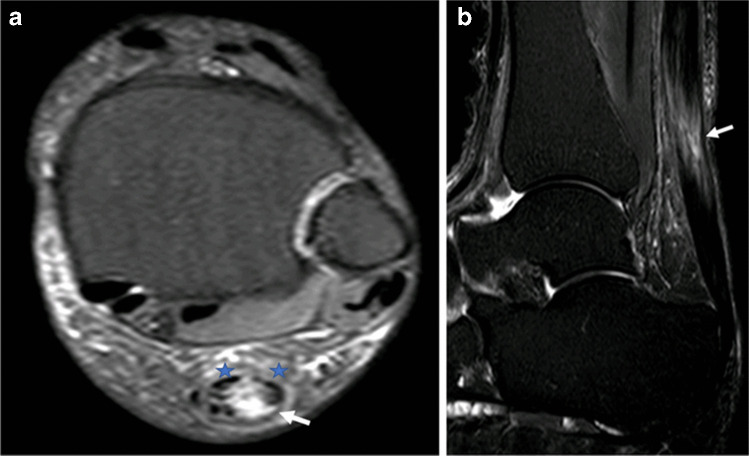

Fig. 3.

MRI of the left ankle in a 51-year-old woman who experienced acute onset severe pain in the distal calf 4 days after an ultrasound-guided peritendinous Achilles corticosteroid injection. Axial (a) and sagittal (b) STIR images of the left ankle demonstrate near complete rupture of the Achilles tendon (arrows) at the musculotendinous junction. Some peripheral fibres remain intact preventing total discontinuity (stars in (a))